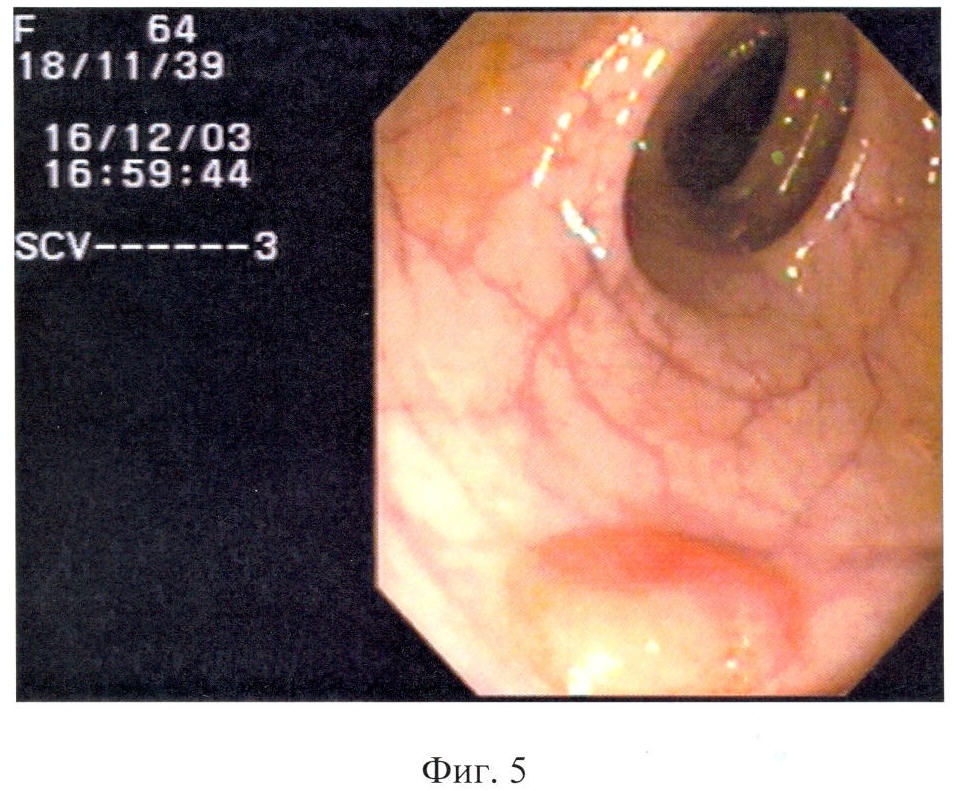

Способ поясняется следующими чертежами, где на фиг.1 показан полип области печеночного изгиба, суммарный балльный критерий более 179: а – при максимальном приближении дистальной головки и линзы колоноскопа, б – после биопсии; на фиг.2 – полип сигмовидной кишки, суммарный балльный критерий до 178 баллов (клинический пример 1); на фиг.3 – полип сигмовидной кишки, суммарный балльный критерий более 179 баллов, на фиг.4 – гистологический срез полипа сигмовидной кишки, окраска гематоксилин-эозином (клинический пример 2); на фиг.5 – полип сигмовидной кишки, суммарный балльный критерий до 178 баллов, на фиг.6 – полип сигмовидной кишки через 10 месяцев после первого обследования, суммарный балльный критерий более 179 баллов (клинический пример 3), а также табл.1, где перечислены эндоскопические признаки, их градации и числовые значения, используемые для вычисления суммарного балльного критерия, и табл.2, где показана морфологическая характеристика полипа и лечебная тактика в зависимости от суммарного балльного критерия исследования.

В области печеночного изгиба расположен полип на широком основании, размером до 0,6 см, розовый, округлый, рыхлый, контактно кровоточивый (фиг.1а, б).

В соответствии с предложенным способом определения вычислен суммарный балльный критерий по эндоскопическим признакам.

Критерий = группа по размеру + эндоскопический тип + цвет полипа + форма полипа + поверхность полипа + ранимость = 81+44+17+12+92+95=341 балл.

Суммарный балльный критерий более 179 баллов означает наличие облигатного предрака или развитие рака. Пациентке предложено выполнение полипэктомии.